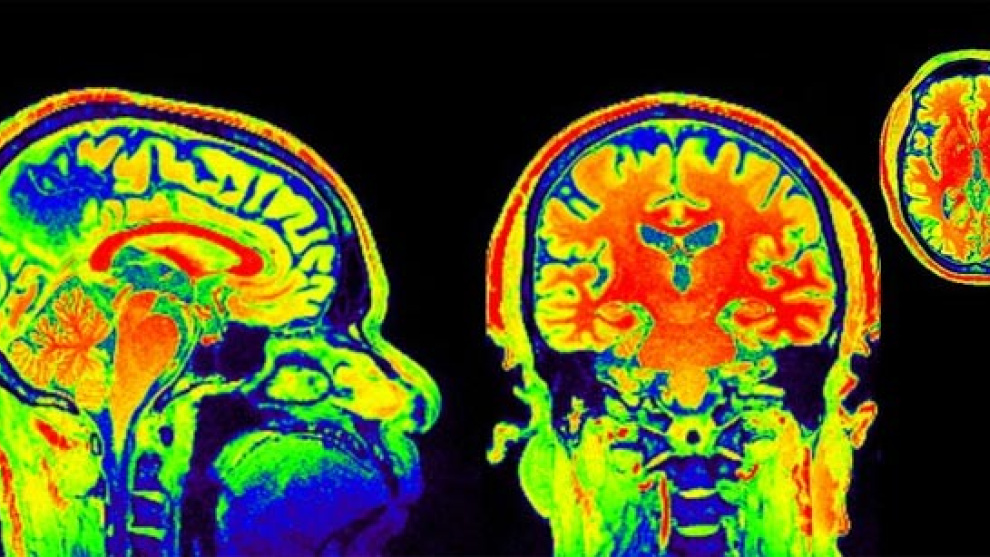

Los investigadores han intentado utilizar técnicas de imagen para verlo, y sí que han encontrado indicios de cambios cerebrales

Los investigadores han intentado utilizar técnicas de imagen para verlo, y sí que han encontrado indicios de cambios cerebrales. Los individuos deprimidos a menudo tiene una actividad exagerada en la amígdala (parte del cerebro implicada en el proceso de las emociones) que no es controlada adecuadamente por la corteza prefrontal, responsable de tareas mentales complejas. Los antidepresivos, piensan algunos investigadores, aquietan la actividad de la amígdala, mientras que la TCC aumenta la actividad y, por tanto, la capacidad de control de la corteza prefrontal. Los escasos estudios existentes indican que se producen cambios cerebrales tras una terapia cognitiva de 14 semanas de duración, pero no son concluyentes y tampoco se sabe si son la causa o una consecuencia de la mejora del paciente. Lo que sí parece es que los cambios son perdurables.